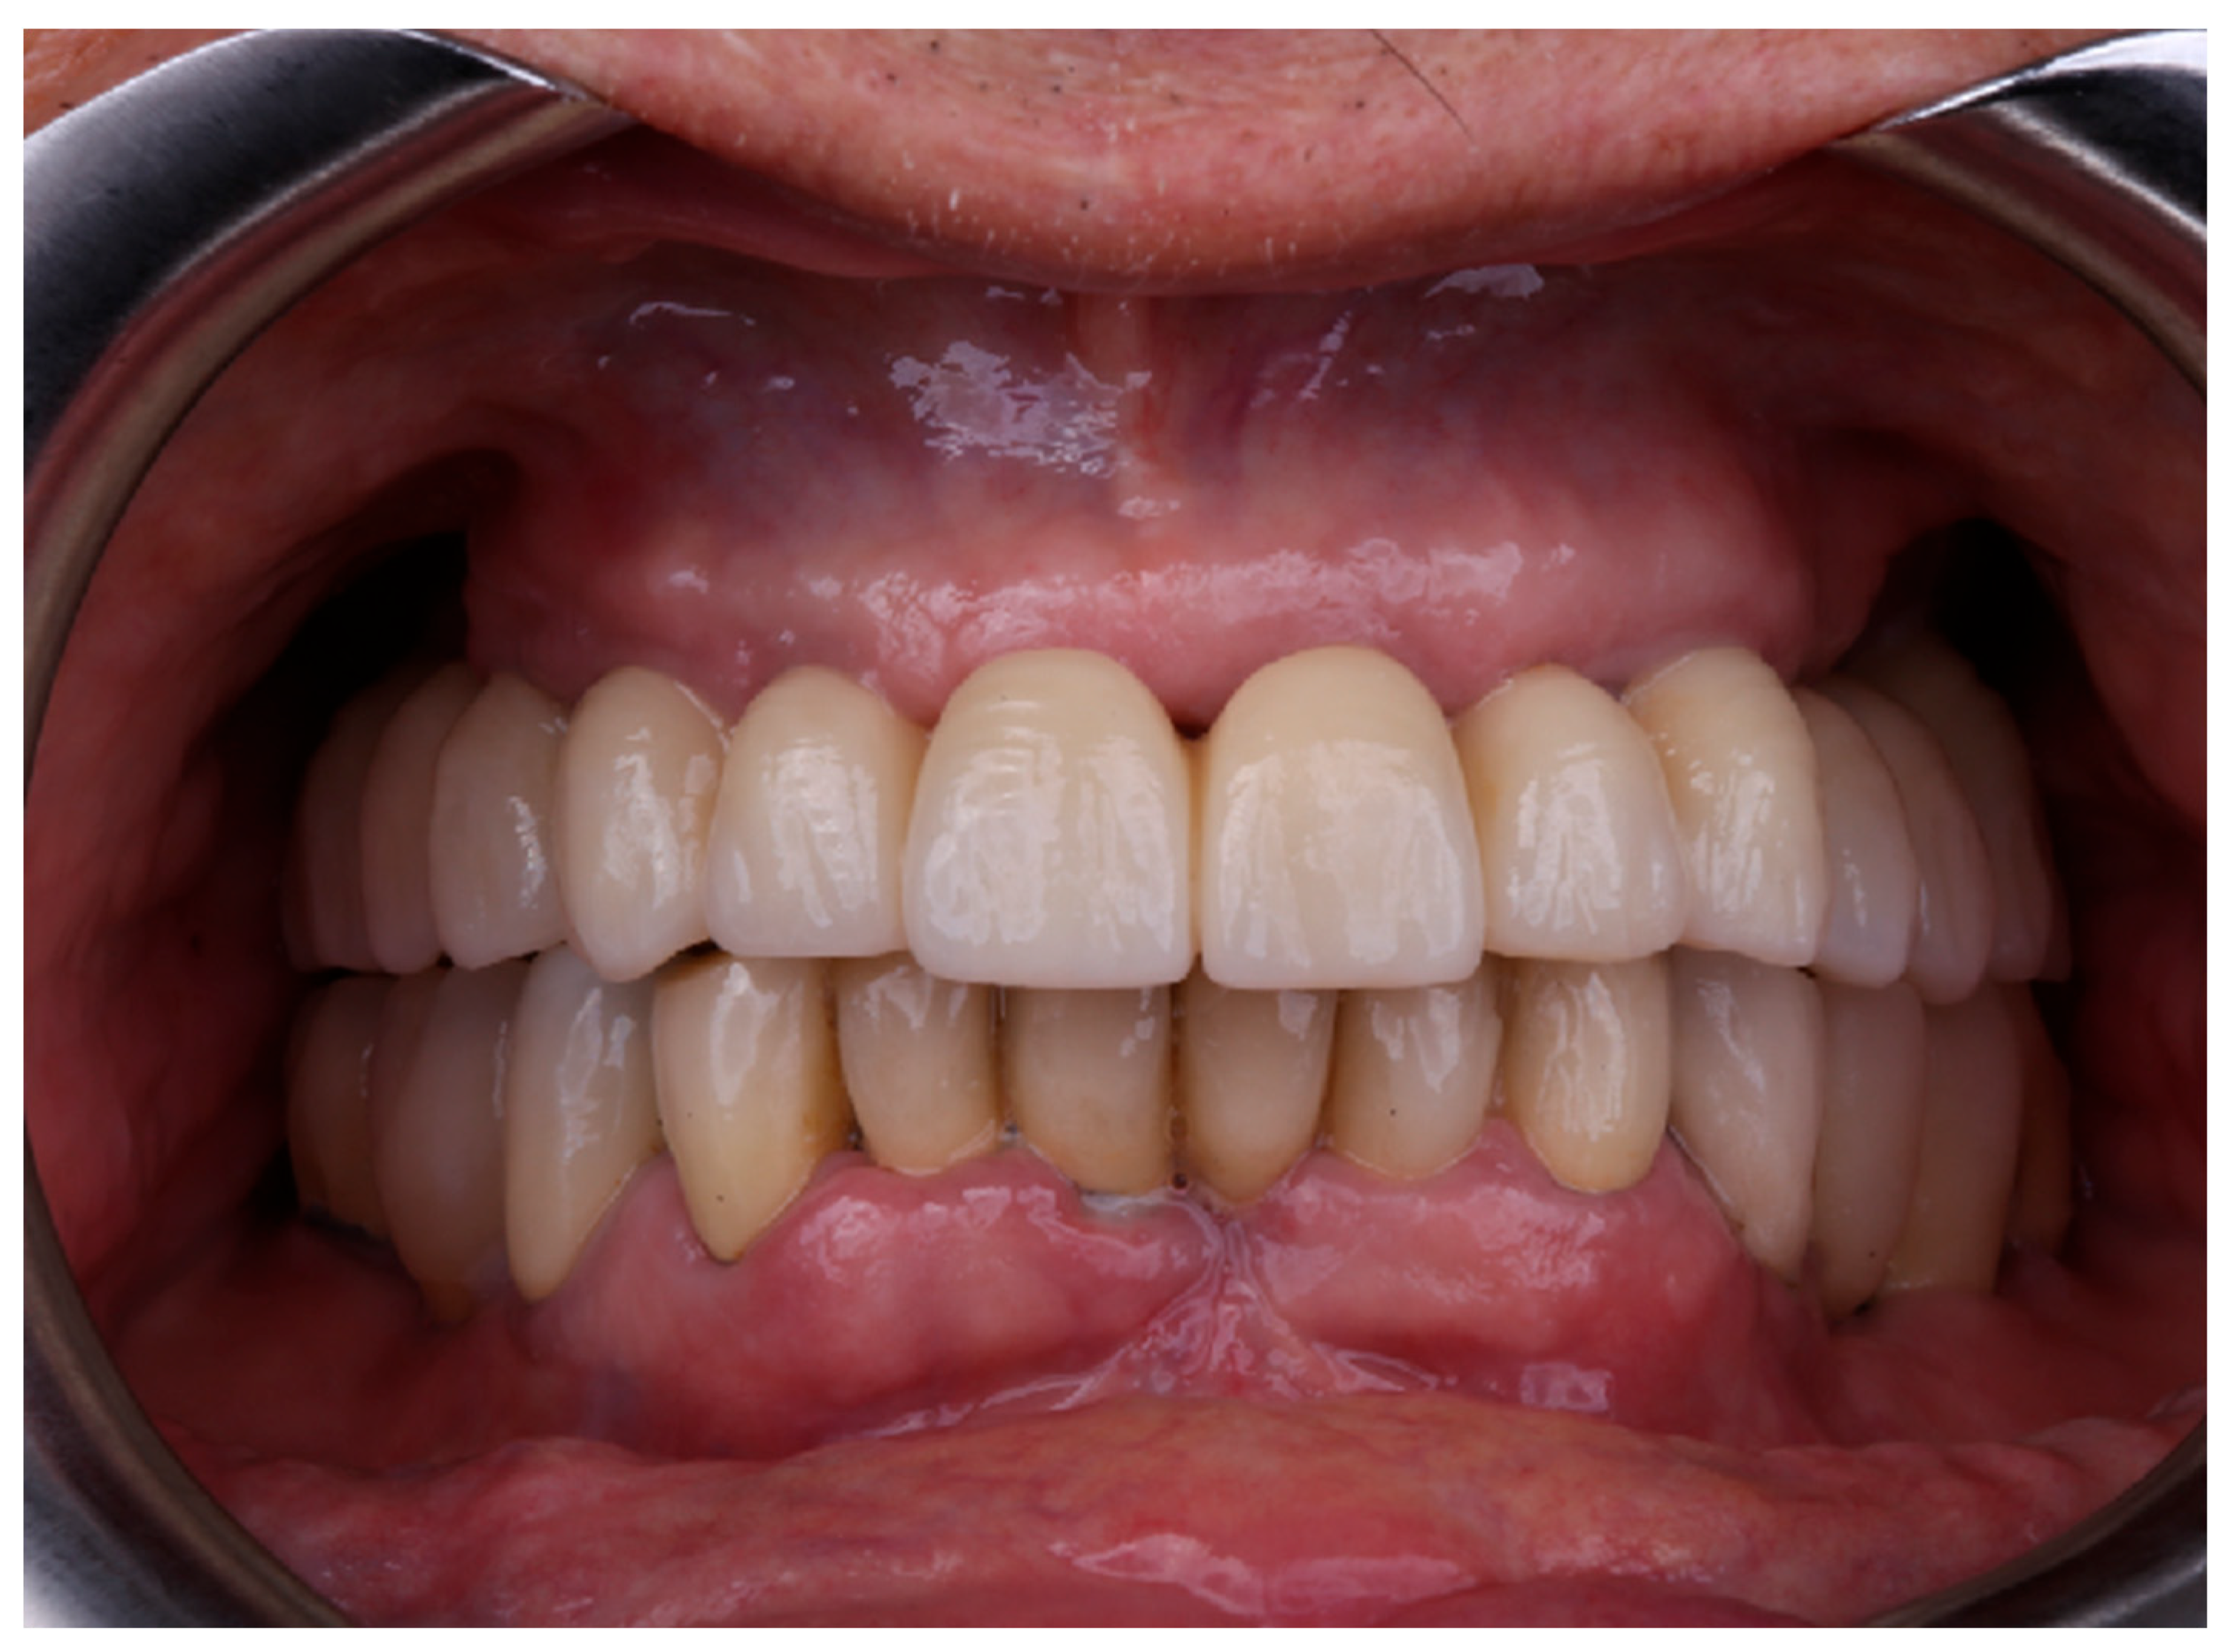

Subsequently, the definitive monolithic zirconia prosthesis bonded to a CAD/CAM titanium bar was delivered following additional visual and tactile verification of passive fit (Figure 4) according to the the screw resistance test. All prosthetic screws were initially tightened to 5 Ncm and then progressively tightened from 5 to 20 Ncm using a calibrated universal torque wrench (TorqControl, Anthogyr).

Figure 4. Definitive prosthesis delivery.